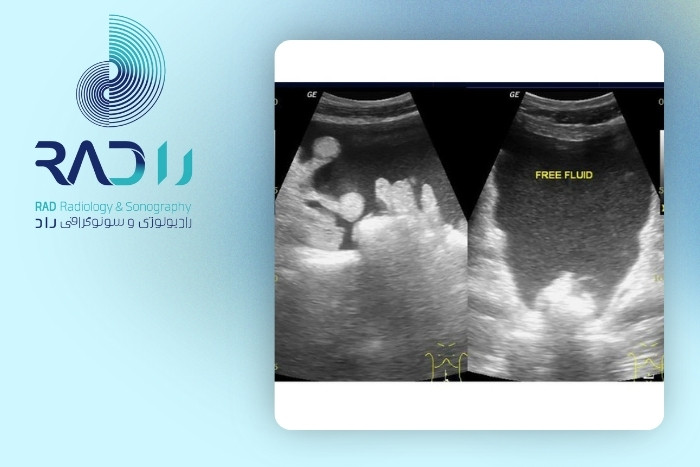

نقش سونوگرافی در شناسایی وجود آب در شکم (آسیت)

سونوگرافی شکم یکی از دقیقترین و در دسترسترین روشهای تشخیصی برای شناسایی وجود آب یا تجمع مایع در شکم است که اصطلاحاً به آن آسیت (Ascites) گفته میشود.

در حالت طبیعی اندامهای داخلی مانند کبد، طحال، روده و کلیه در کنار هم و بدون فاصله مشخص دیده میشوند اما اگر بین این اندامها مایع جمع شده باشد پزشک در سونوگرافی نواحی تیرهرنگ (Hypoechoic) مشاهده میکند که دقیقاً نشانه وجود آب در شکم است.

اولتراسوند نهتنها وجود مایع را نشان میدهد بلکه موارد زیر را هم مشخص میکند:

مقدار تقریبی آسیت: از چند میلیلیتر تا چند لیتر مایع را میتوان تشخیص داد.

محل تجمع مایع: مثلاً فقط اطراف کبد، در لگن یا بهصورت منتشر در تمام شکم.

نوع مایع: سونوگرافی میتواند تشخیص دهد مایع شفاف است یا غلیظ (نشانه عفونت یا تومور).

تأثیر بر اندامها: آیا فشار مایع باعث جابجایی احشاء شده است یا نه.